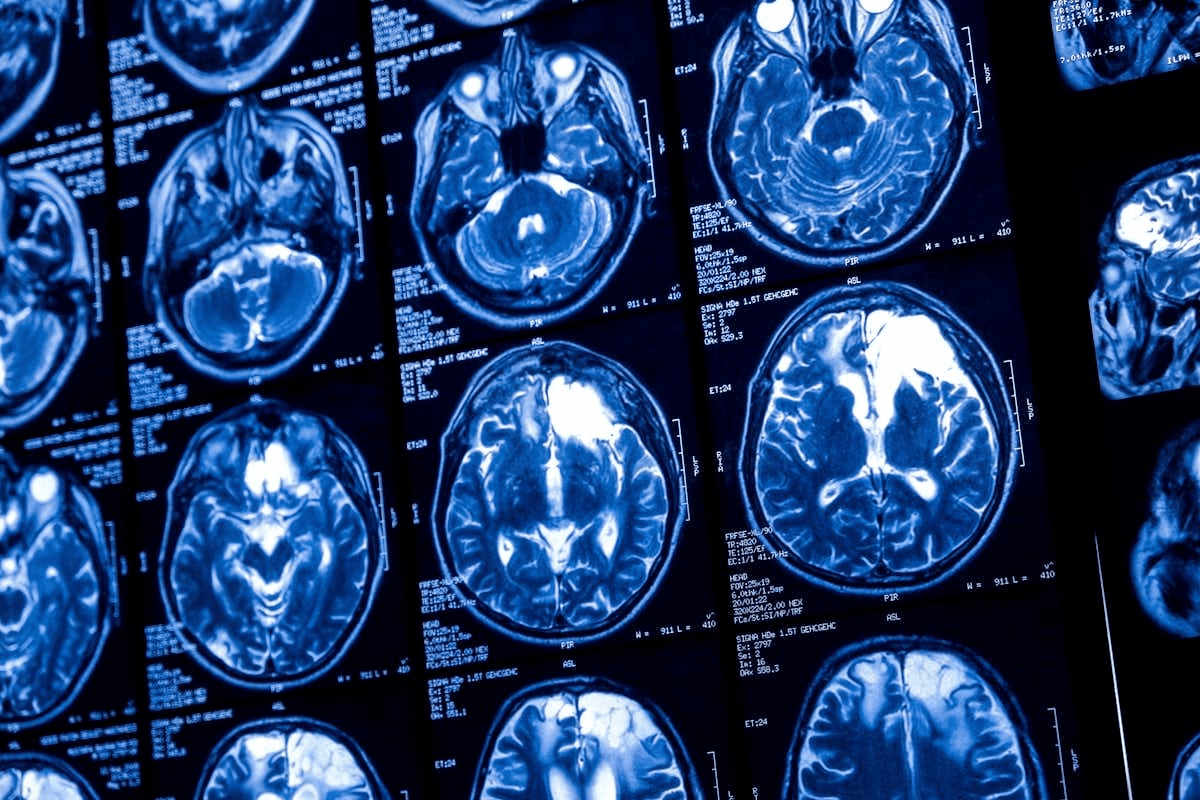

Imaging Requirements for EVT Candidacy

Imaging is key in deciding if someone can have EVT. Doctors use CT angiography (CTA) and MR angiography (MRA) to see the blocked blood vessel and how much brain tissue is at risk.

| CT | Assess early ischemic changes |

| CTA | Identify occlusion site and collateral circulation |

| MRI | Evaluate infarct core and penumbra |

A recent study found that new imaging methods have changed how doctors pick patients for EVT. Now, they can spot who will really benefit from the treatment more accurately.